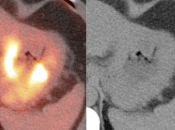

The difficulty with PET/CT imaging and gastric cancer is that it is both easy to overlook and easy to over-call.

Normal FDG uptake involving the stomach can be extremely variable. It is not uncommon to see diffuse intense uptake throughout the entire stomach or intense uptake limited to only a segment of the stomach (fundus, body or antrum).

In general, we raise a suspicion of gastric malignancy if:

• Focal or regional hypermetabolic activity is accompanied by at least the suggestion of associated wall thickening (often difficult to assess if the patient’s stomach is suboptimally distended with water or oral contrast);

• Uptake is extremely focal (more likely to represent malignancy or ulcer);

• Focal/segmental uptake is extremely intense.